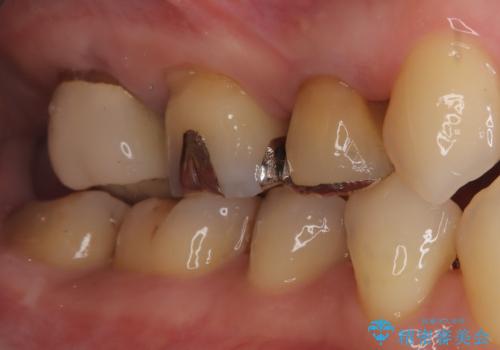

- 古い被せ物をやり変えたいことを主訴に来院されました。

根管治療も行い、きれいな被せ物になり患者さんも喜んでいました。

3本まとめて治療をすることで来院回数を減らし、患者さんの負担を減らすことができ喜んでいただけました。